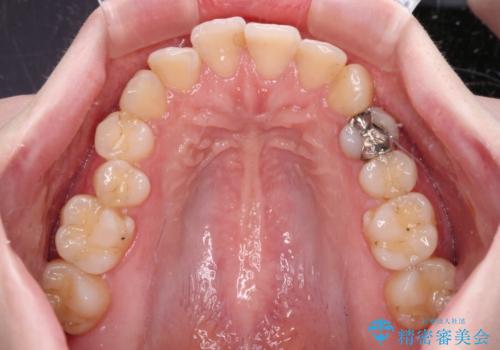

開咬と前方に飛び出した前歯 インビザラインによる矯正治療

- 上下前歯の非接触と叢生を気にして来院された患者様です。

開咬の改善はインビザラインの最も得意とするところであるため、インビザラインを用いて矯正治療を行うこととしました。

舌の突出癖改善のトレーニングをしっかりと行っていただき、上下前歯が接触する咬み合わせを達成することができました。